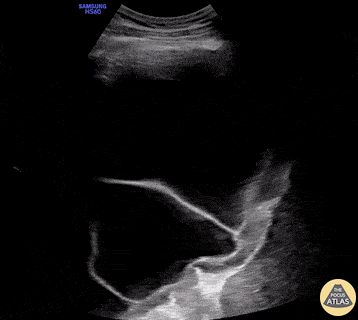

Pulmonary - Septated Pleural Effusion

76yo male with shortness of breath on exertion, w/o fever or other signs of infection. POCUS showed a large septated unilateral pleural effusion. Note the irregular and thickened pleura adjacent to the diaphragm (right). Thoracentesis was only partially successful with a large residual effusion after drainage of 1000ml of exudative fluid with signs of lymphocytic inflammation w/o malignant cells on cytopathologic analysis. Thoracoscopic biopsy confirmed the diagnosis of a pleural mesothelioma 60 years after exposure to asbestos. The presence of a septated complex effusion is 94% specific for an exudative effusion and warrants further investigation (Shkolnik, 2020). Cytopathology of pleural fluid is often negative in malignant mesothelioma and pleural biopsies are needed to confirm the diagnosis (Porcel, 2014). Victor Speidel Langenthal Regional Hospital, Switzerland